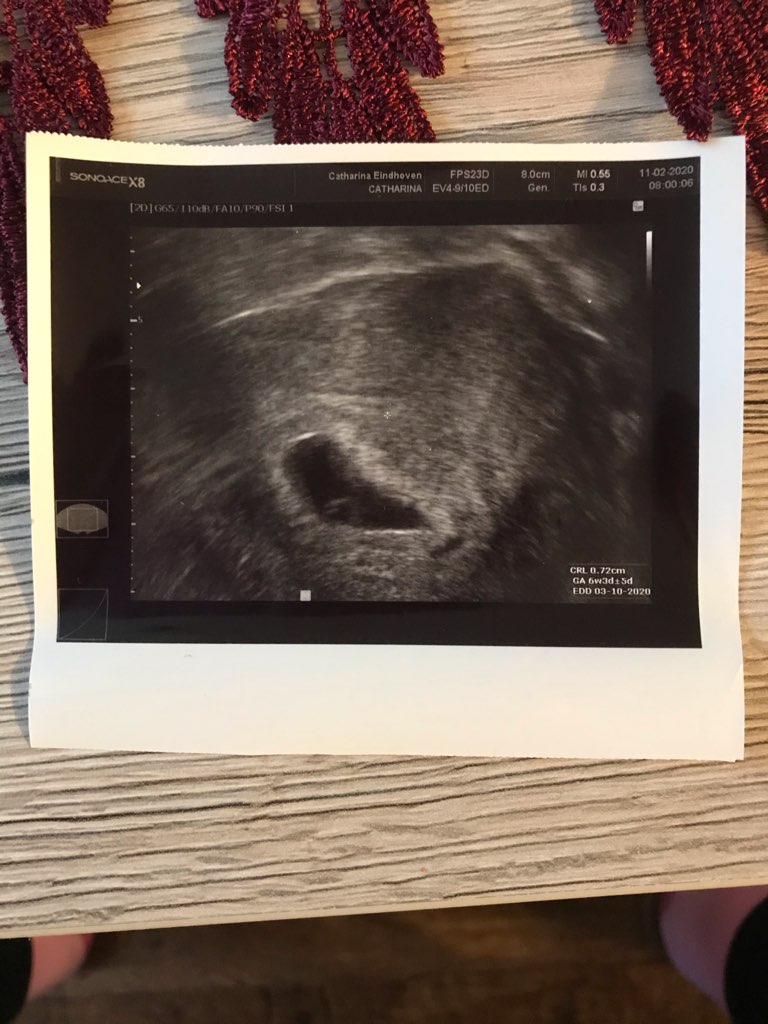

Pomiędzy tymi dwoją usg jest tydzień różnicy 26dpt i 33dpt na drugim widać już zdecydowanie ładnie pecherzyk zoltkowy i zarodek z sercem

• IMG_1903.jpeg

IMG_1903.jpeg

146,1 KB · Wyświetleń: 68